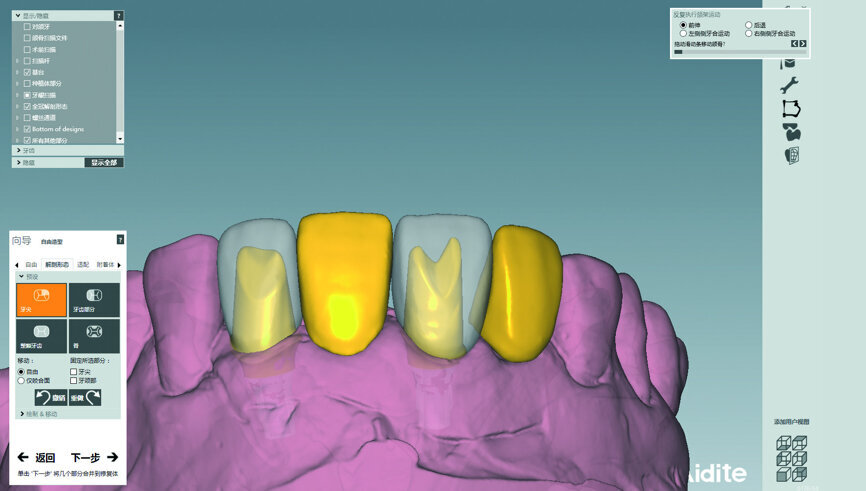

The cast model was scanned step by step to obtain a digital model and this was integrated with a virtual articulator. The anterior guidance of the virtual articulator was set according to the data from the provisional restoration. Next, the design was completed on computer and the titanium-based zirconia abutment and fixed zirconia bridge produced via CAM. After staining and glazing, the final restoration was completed (Figs. 34–41). The final restoration demonstrated a good outcome, both aesthetically and functionally (Figs. 42–50).

When manufacturing the final restoration, a CAD/CAM system was used. Digital models, ICP relationship and data on anterior guidance were integrated into the virtual articulation system. In the process of CAD, the precise design of both aesthetic and functional aspects could be realised.

Fig. 37: Design of the abutment.

Fig. 38: Design of the bridge.